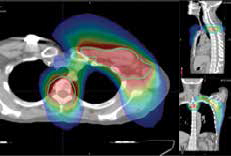

Radiation was delivered to the left chest wall, internalmammary chain, left supraclavicular fossa and medialaxilla of this patient with the TomoTherapy System.

In the summer of 2012, a 52-year-old female, referred from another radiation center, presented with a large multifocal (ER+/PR+ Her2+) infiltrating ductal carcinoma in the left breast. She had previously undergone mastectomy and chemotherapy, followed by radiation to the left chest wall, internal mammary chain, supraclavicular fossa, medial axilla and the T2-T4 vertebral bodies.

“The ability to deliver highly conformal plans to complex tumors and avoid normal structures is extremely useful,” added Landis. He and his team selected TomoTherapy to “concurrently treat [the patient’s] oligometastatic lesion alongside the standard fields while maintaining safe dose volume constraints.” After the treatment, the patient developed no late effects and remained without evidence of recurrence at 24 months.